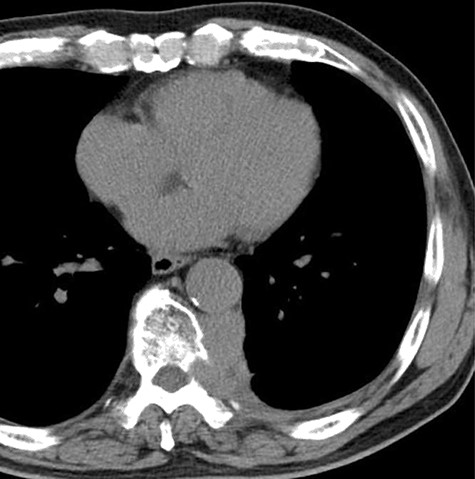

A 78-year-old man complained of chest pain for 2 months and was admitted to our hospital. Computed tomography (CT) scans revealed a tumor in the left thorax. He had undergone prior surgical resection of the primary SFT and recurrent tumor at 11 and 2 years before the current presentation. The CT findings of the primary tumor revealed a solitary, well-circumscribed and no signs of invasion (Fig. 1). Intraoperatively, the primary tumor arose from the visceral pleura and the resection was performed by wedge resection. The resected tumor was an oval, elastic soft mass with homogenous milky white cut surfaces. Postoperative histopathologic and immunohistochemical findings were consistent with SFT, and the mitosis and malignant features, including nuclear atypia, necrosis or higher cellularity, were hardly seen. In contrast to the primary tumor, as shown in Fig. 2, the CT findings revealed that the current tumor extended through the neural foramen. Furthermore, the tumor had an osteoclastic progression into the thoracic spine. Therefore, this tumor was considered to become malignant, and we considered the surgical complete resection is impossible. For histological confirmation, CT guided needle biopsy was performed. The histological findings of this recurrent tumor were identical to those of the primary tumor. The mitosis was hardly seen in this recurrent tumor. However, immunohistochemically, the MIB-1 proliferation index (Ki-67) of the primary tumor and the current tumor was 1.74 and 30.00%, respectively (Fig. 3A and B).

The computed tomographic findings of the primary tumor (arrow).